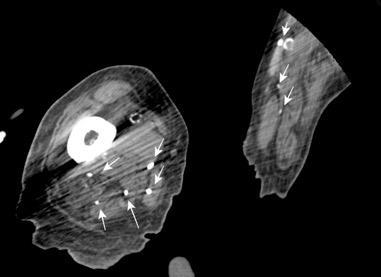

10-20% de pacientes las larvas alcanzan la circulación sistémica y pueden llegar a cualquier órgano También pueden llegar a órganos intrabdominales por migración transmural.

Yagmur Y et al. Unusual Location of Hydatid Cysts: A Case Report and Literature Review. Int Surg. 2012 / Pedrosa I et al. Hydatid disease: radiologic and pathologic features and complications . Radiographics 2000.